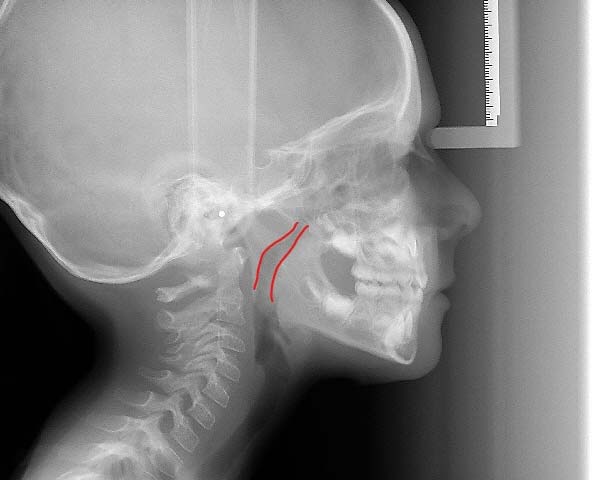

The best age is as soon as it is suspected there are airway issues, our youngest patient is 2.5 years old. The sooner we recognize an airway issue, the greater the chances of achieving harmonious physical and neural growth and development. Below are examples of patients in our practice who have undergone airway development for pediatric sleep apnea or sleep disordered breathing:Adults